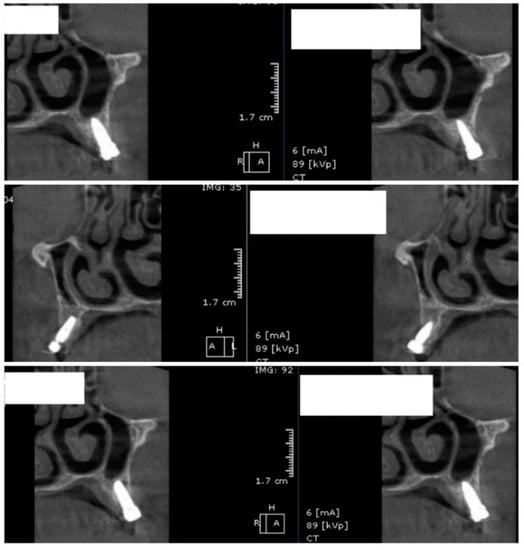

Image showing the bone density measured in Hounsfield units (HU) as well as the standard deviations of the volume.

Each voxel of the CBCT volume is characterized by a CT number, expressed in HU (Hounsfield Units). The software displays the mean value of the CT numbers of the constituent voxels and the standard deviation of these CT numbers (Figure 5).

After 60 days of healing process, new CBCT images were recorded in order to assess bone density changes that might have occurred near the implant sites (Figure 9, Figure 10 and Figure 11).

Random CBCT sections with pulse electromagnetic healing caps in position.

Figure 11.

Random CBCT images with pulse electromagnetic healing caps in position.